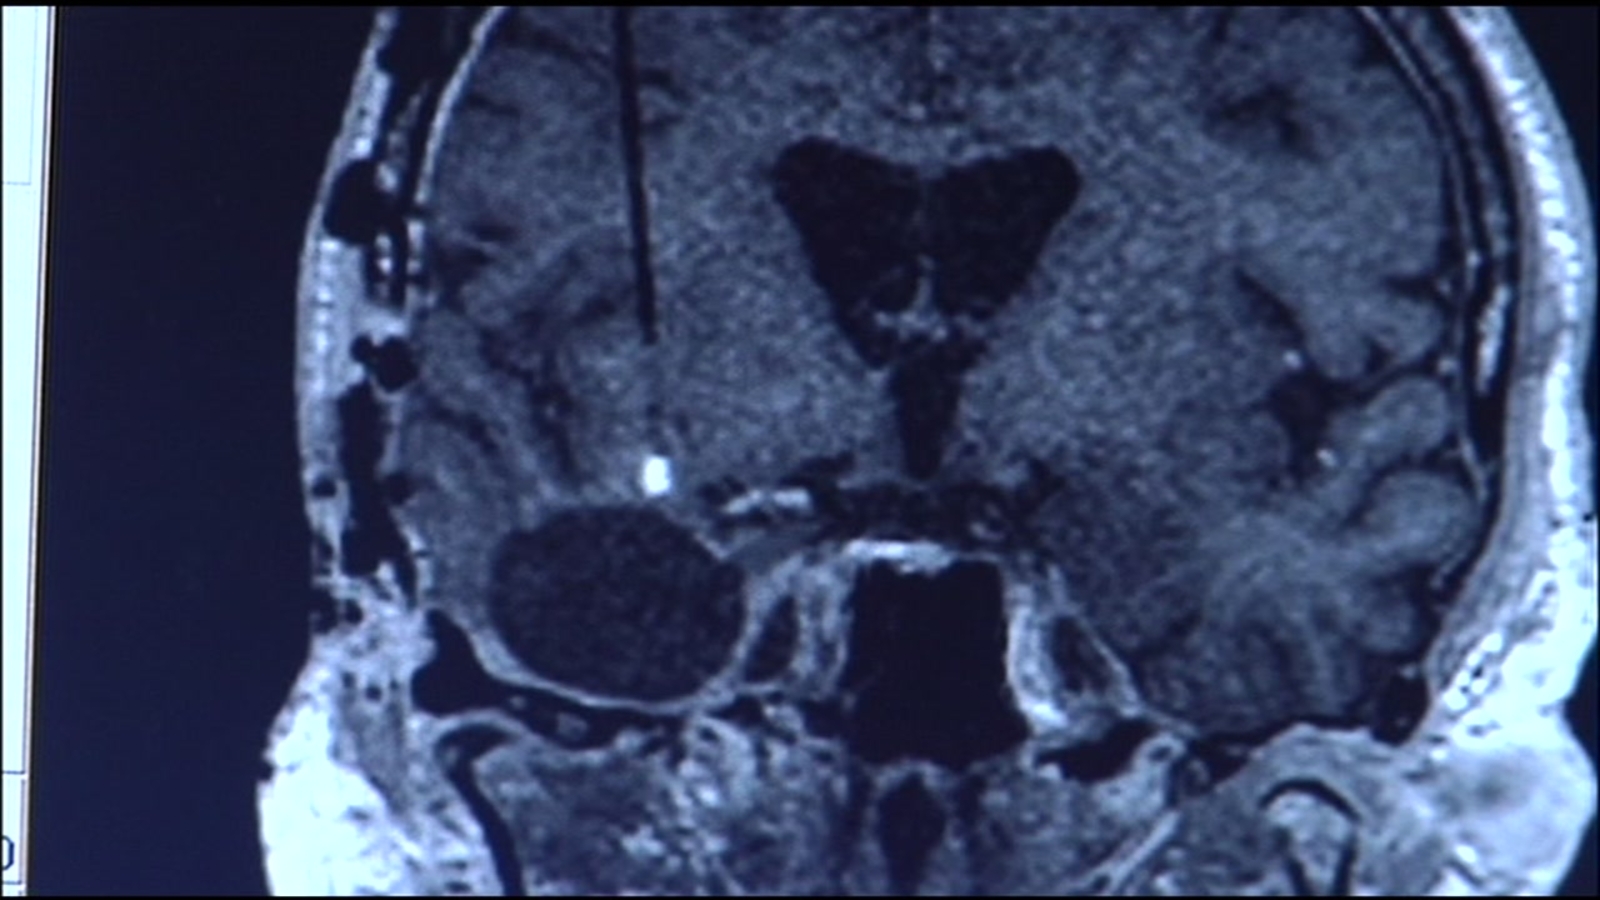

"People aren't being legitimized, and they're very real neurologic disturbances they're having after COVID," said USCF neurologist, Dr. Joanna Hellmuth.

She says the "disturbances" mirror symptoms from other viruses. "If I didn't know in advance if one of my patients had HIV or COVID, I wouldn't be able to tell you the difference between the two it's so similar."

Dr. Hellmuth recently published a study that shows 20% of her the participants had persistent cognitive symptoms after COVID infections. "These problems seem to be quite common." She says her study was based on 100 patients, none of whom had been hospitalized. Their ages ranged from 35-56 and the median age was 39.

Dr. Hellmuth says part of the struggle with diagnosing these symptoms is that most screening tools are geared towards identifying dementia and are not picking up COVID-related brain changes. She says physicians should refer patients for neuropsychological testing if they are reporting these types of symptoms post COVID.